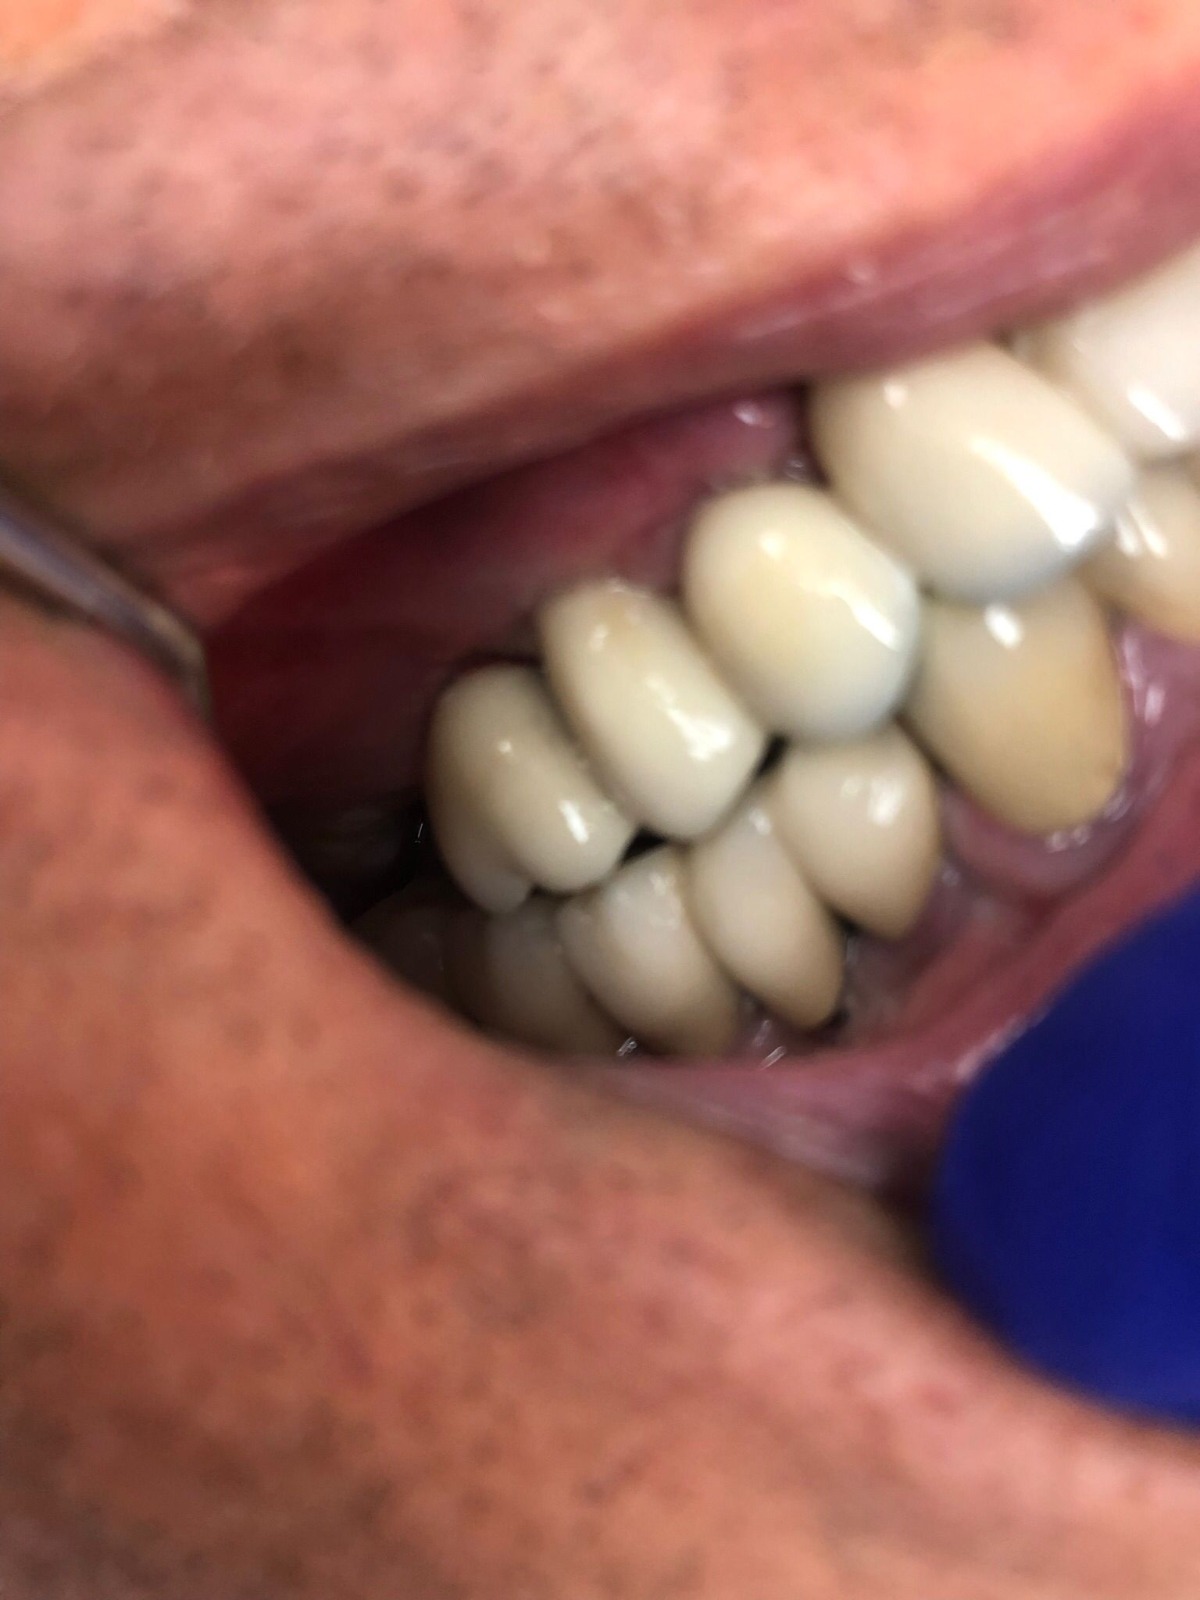

Actualmente vuelve el paciente de nuevo con la misma prótesis. Había roto dos de los tres pilares en concreto los más distales. El primero de los dos había roto la rosca del aditamento dentro del implante como ocurre habitualmente. Pero el ultimo pilar había roto directamente la cabeza del implante tal como se ve en la radiografía y lo que quedaba era un cilindro de titanio macizo perfectamente integrado en el maxilar, sin posibilidad de enroscar nada. Le explicamos al paciente que habría que quitar y poner un implante en el mismo acto. El paciente dijo que no, así que decimos que no se haría cirugía. Buscamos solución alternativa: hacemos un un agujero en el centro del macizo cilíndrico del implante roto y pasamos sucesivamente el set de machos roscantes. Utilizamos una fresa cañón de 1 mm que poco a poco se va introduciendo hasta 8mm con un poco de vagación, que hace que sea un poco mas de 1mm de diámetro. Posteriormente pasamos el conjunto de machos roscantes de métrica 2mm para poder usar un aditamento experimental, que era un palo de rosca de diámetro 2 mm unido a un cuerpo metálico en forma de sombrero napoleónico fabricado en cromo/cobalto, prototipos primitivos de la sistemática ASATIM y que tienen la característica de tener gran resistencia a la fractura. Nos llevó un tiempo largo el tallado de dichos aditamentos, tal como se puede observar en las imágenes, y tras cicatrizar la encía se le hizo una prótesis estándar. Esperemos que no lo rompa más veces.